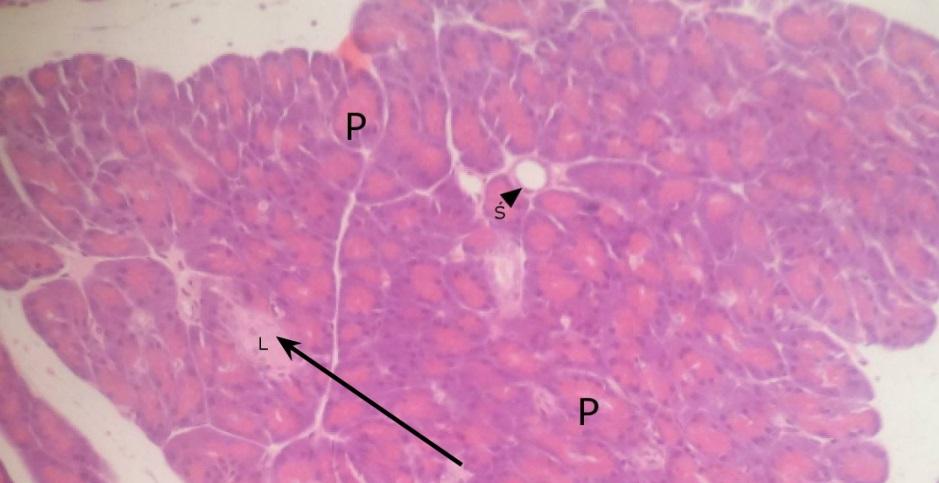

wyspa Langerhansa (trzustka)

pęcherzyk surowiczy (trzustka)

przewody śródpłacikowe - wstawki z nabłonkiem jednowarstwowym walcowatym (trzustka)

przewód międzypłacikowy z nabłonkiem jednowarstwowym walcowatym (trzustka)